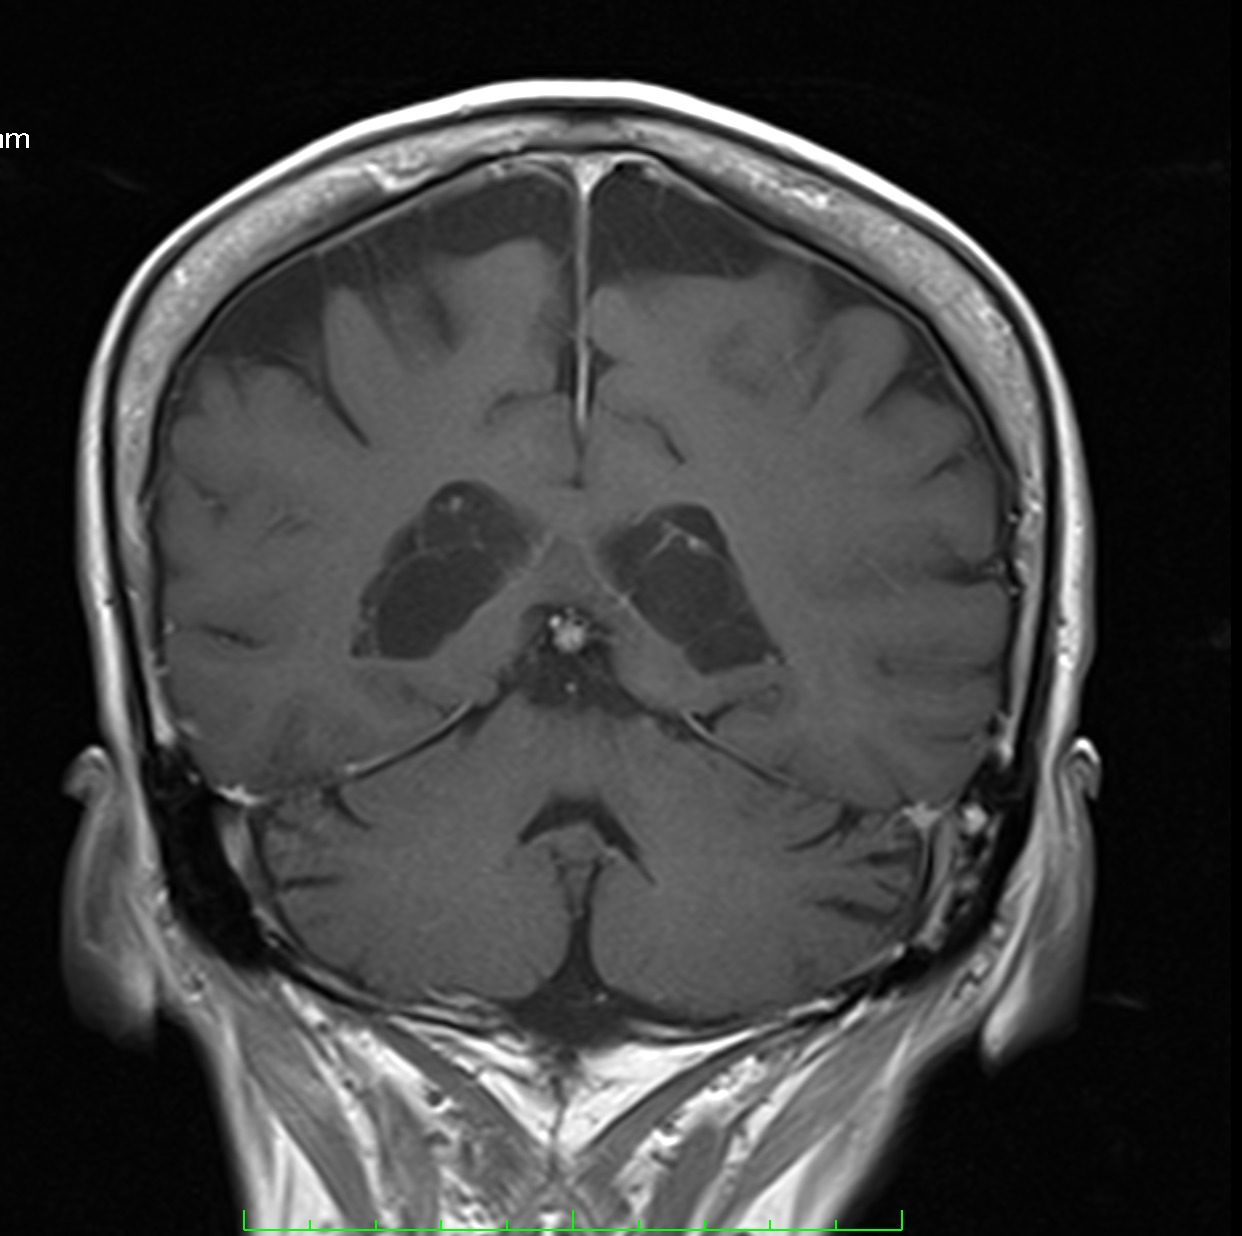

Son pseudolesiones frecuentemente observadas en estudios de neuroimagen.

Sus principales características son:

✔ Lesiones intraventriculares

✔Bilaterales

✔65% restringen en la secuencia de difusión

✔ Realce variable posterior a la administración de medio de contraste

✔ No hay edema del parenquima adyacente

NO DEBEN CONFUNDIRSE CON LESIONES TUMORALES INTRAVENTRICULARES!!!!